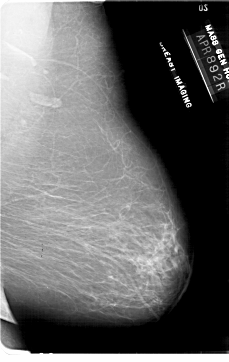

A_1862_1.RIGHT_MLO

RIGHT_MLO LINES 6871 PIXELS_PER_LINE 4336 BITS_PER_PIXEL 12 RESOLUTION 43.5 NON_OVERLAY